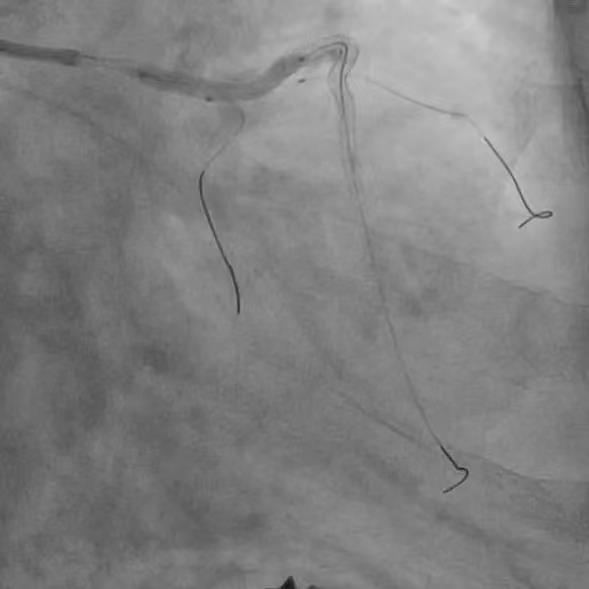

IABP植入后,旋磨导丝顺利经左主干通过病变置于LAD远段,先后使用1.5mm、1.75mm磨头旋磨,而后,在分支均保护的情况下,植入3.0*24mm支架,并选择3.5*12mm NC 30atm行后扩。![]() 先后1.5mm、1.75mm磨头旋磨 ![]() 分支均保护的情况下,3.0*24mm支架植入 然而,虽经NC球囊反复后扩张,左主干支架依然膨胀不良,考虑为钙化厚度过大所致。此时,再行球囊扩张无效、再行旋磨磨头直径不够;为求进一步管腔获得,果断启动Shockwave IVL。为保证IVL球囊与支架及深层钙化紧密贴靠,选取3.5*12mm Shockwave IVL球囊,通过病变后,迅速充盈电解液并扩张至4atm,触发血管内冲击波,每周期10个脉冲、耗时10秒,共行6个周期IVL治疗,之后将脉冲球囊扩张至6atm。复查造影及IVUS,主干最小管腔面积从4.9mm2上升为7.3mm2。随即又在前降支的中远段重度狭窄处顺利植入了2.5*18mm的支架。患者于三天后顺利出院,胸闷症状明显改善,活动耐量显著增加。 ![]() ![]() ![]() 3.5*12mm Shockwave IVL左主干支架内处理前后对比 术者总结